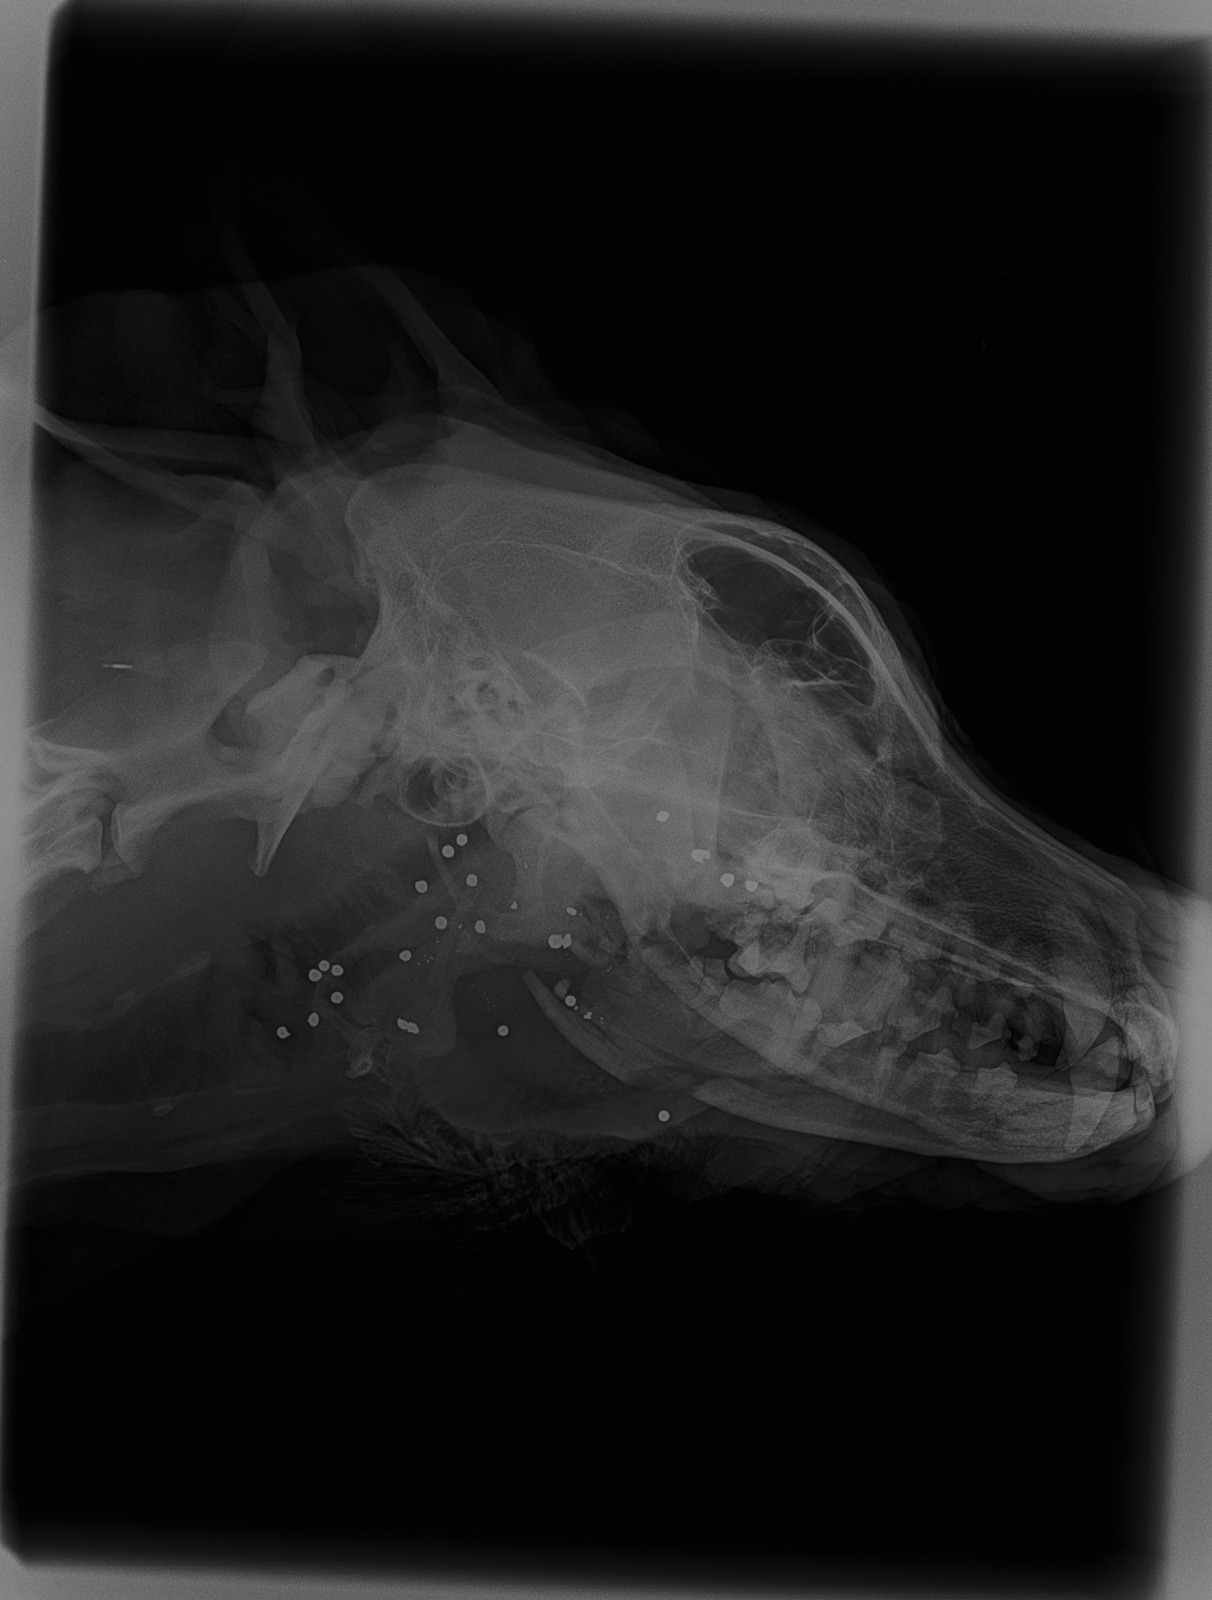

Dada la gravedad, magnitud y evolución de la herida, se sospecha que las lesiones fueron producidas intencionadamente, con maldad y alevosía, y se produjeron en varias ocasiones. No se sabe lo que le hicieron, pero piensan que el primer golpe le destrozó la mandíbula y la boca por completo y debió ser con algún objeto contundente y duro. Al no conseguir “acabar con su vida”, le dispararon varias veces, desde muy corta distancia, en la cabeza (que son las balas que se ven en sus radiografías). Recibió muchos disparos, lo que acabó por destrozarle la mandíbula, el maxilar, los huesos nasales y la boca.